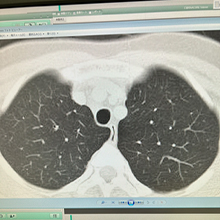

喘息専門外来